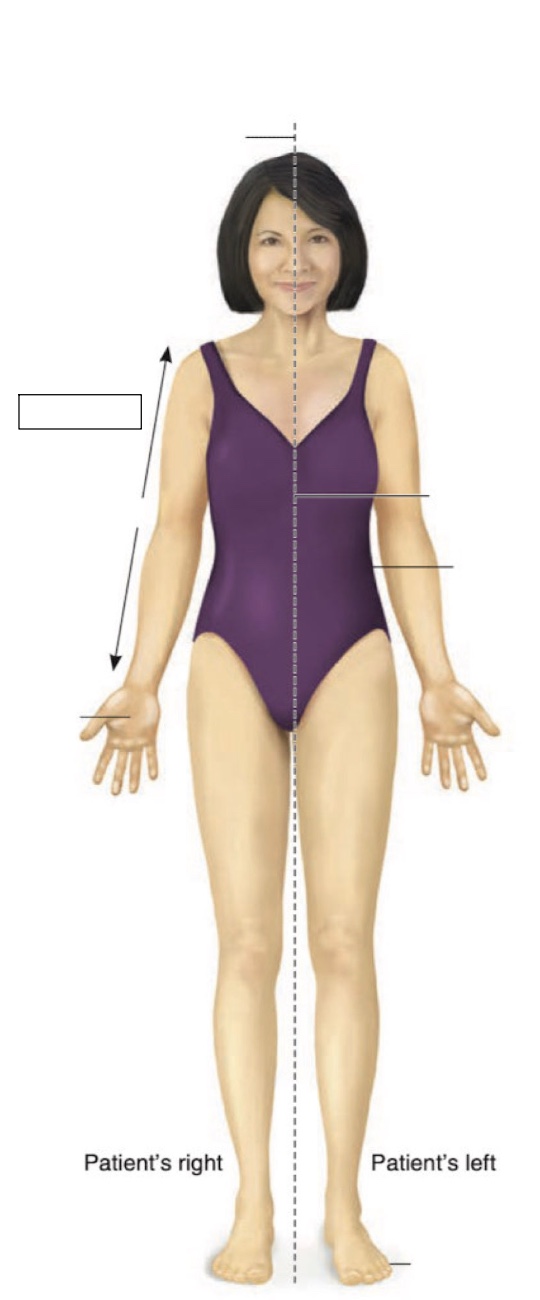

Anterior

Superior

Inferior

Midline

Medial

Lateral

Cranial region

thoracic region

umbilical region

inguinal region

genital region

femoral region

arm

forearm

cubital region